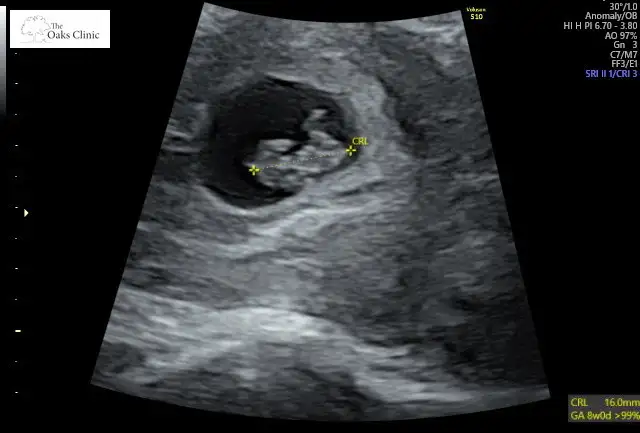

Merhabalar banada bakabilirmisiniz lütfen 5+2 karından